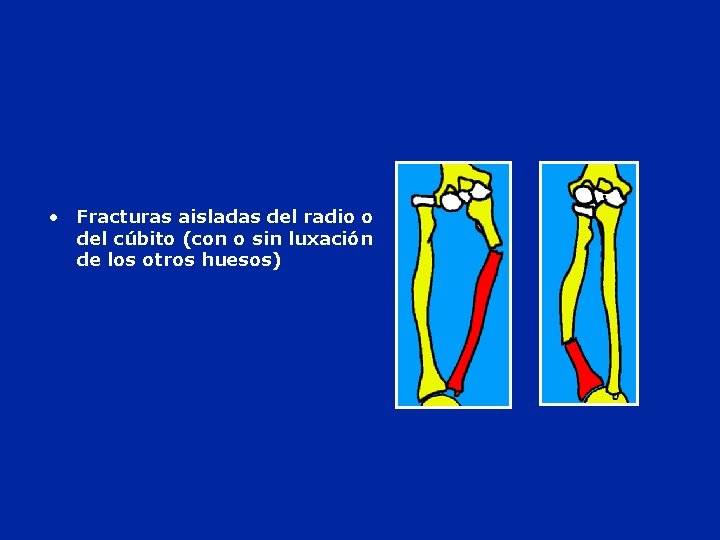

• Fracturas aisladas del radio o del cúbito (con o sin luxación de los otros huesos)